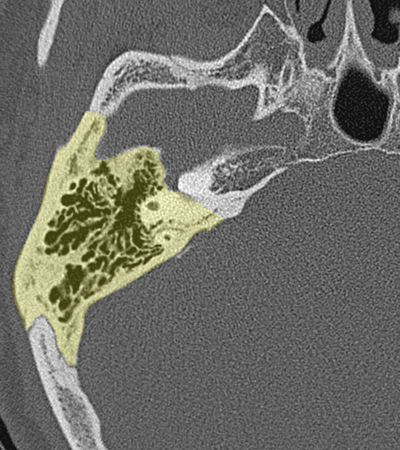

Temporal bone Petrous apex Sphenoido-temporal suture Occipitotemporal suture Petroclival suture

Radioanatomy of Temporal bone